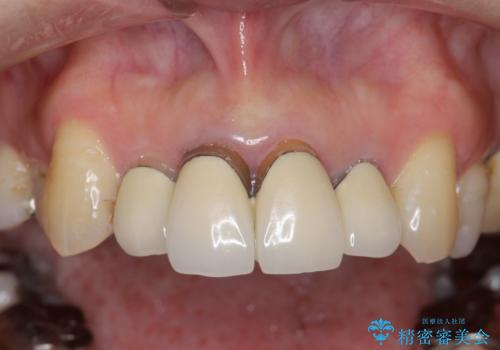

歯茎の黒ずみがきになる 前歯の見た目を改善したい

- クラウン周りの黒ずみが気になり、審美性の改善を求めて来院されました。

以前に治療した前歯クラウンは月日が経過することで劣化・歯肉の位置変化を引き起こし審美障害を引き起こしています。